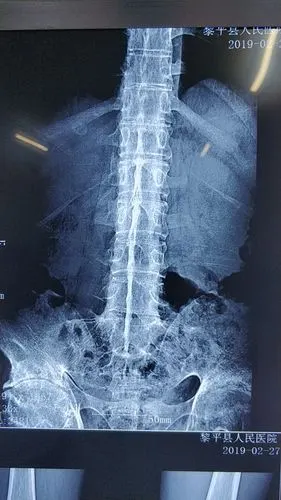

强直性脊柱炎并发症有哪些

强直性脊柱炎可出现以的11种症状

说说强直性脊柱炎

您是否会辨认强直性脊柱炎疼痛原因?

年轻人腰背疼痛,不一定是腰突!警惕强直性脊柱炎

强直性腰椎炎(什么是强直性脊柱炎)